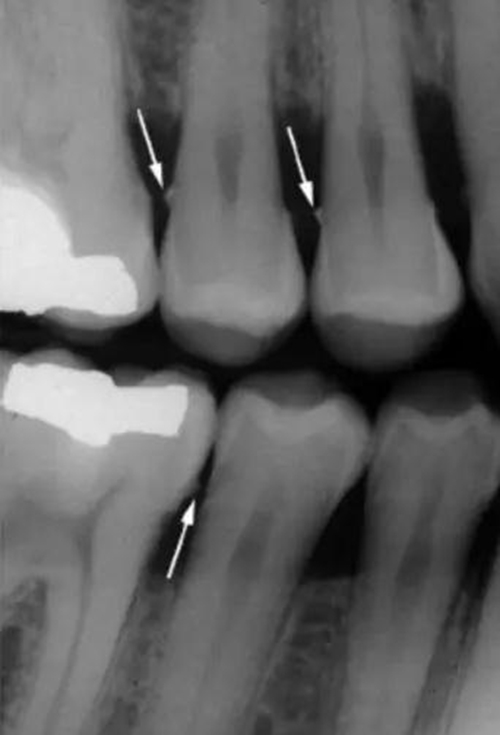

垂直咬翼片更適合牙周檢查。因?yàn)檠乐懿』颊咄ǔS泄俏?,如果吸收?yán)重,水平咬翼片可能沒法顯示牙槽脊,而這時(shí)垂直咬翼片就顯示了其優(yōu)點(diǎn)。

4.jpg

圖 4 水平咬翼片,對有嚴(yán)重骨吸收的患者無法顯示牙槽脊(X 光片取自筆者治療過的病人)